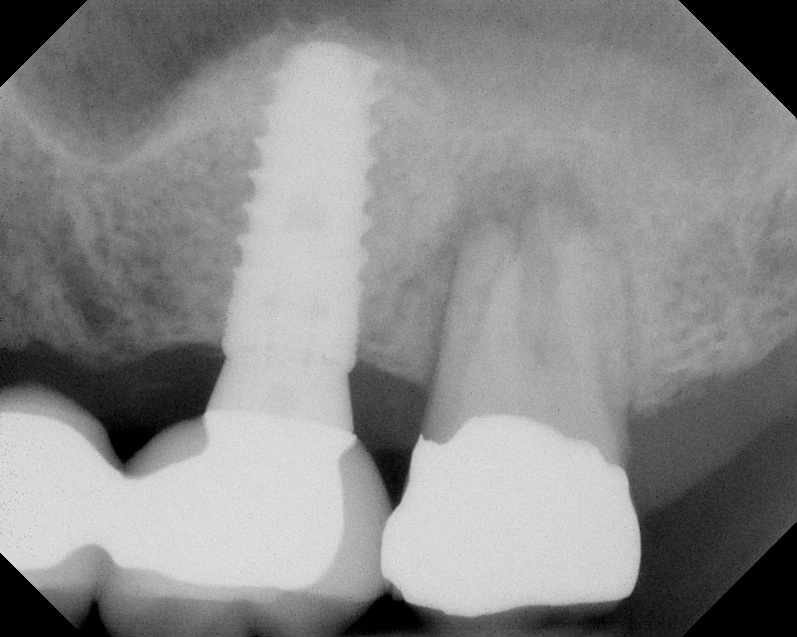

The implant is then delivered and should be well stabilized in the bone. If there is any mobility of the implant, it can either be placed a little deeper (if there is enough native bone) or the implant can be removed and the procedure aborted, in which case it would be a two-stage procedure. This should rarely occur with the tapered designed implant, even with only 2 mm of native bone. Using a bone-level platform-shifting implant (or a tissue-level designed implant) is critical, as the hard and soft tissue will establish a biologic width. If an external hex type of implant is used and the shoulder is placed at the bone level, an expected bone loss of 1.5 mm to 2 mm will occur.24 Figure 10 shows proper bone-level implant depth placement with a platform-shifting design. In this case, a 3-mm healing abutment was placed at the time of surgery to avoid a secondary uncovering surgery, but an implant-level healing abutment could have been placed instead. As can be seen, there was only about 2 mm to 3 mm of native bone height. The membrane was raised about 8 mm to 9 mm. Comparing the radiograph on the day of surgery (Figure 10) to the 6-month postoperative radiograph (Figure 11) shows no loss of native bone, as well as the positive change in appearance of the grafted bone. The 3.5-month CBCT scan (Figure 12) shows good healing of the bone with no coronal bone loss. With minimal native bone present, as in this case, the use of a non-platform-shifting or non-tissue-level implant design could be problematic. After 1.5 mm to 2 mm of crestal bone loss, an external hex designed implant could develop instability with possible implant failure. If a non-tapered implant is used and bone loss occurs during healing, migration of the implant into the sinus could potentially occur. The surgeon can use either a healing abutment or implant-level closure screw over the implant shoulder. With patients who tend to use their tongues to explore or play with the area, or if the area is under a removable partial denture, a closure screw is recommended.

Radiograph of implant N o. 3 and sinus augmentation, day of placement. There is about 2 mm to 3 mm of native bone, and the sinus has been raised about 8 mm to 9 mm.

Fig. 10

A 7-month postoperative radiograph of the restored implant No. 3.

Fig. 11